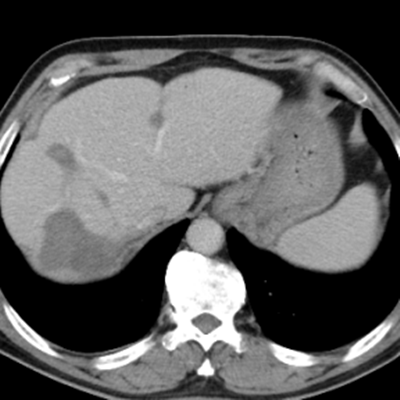

治療后:未見明顯活性轉(zhuǎn)移腫瘤

經(jīng)過兩次肝臟轉(zhuǎn)移瘤射頻消融手術(shù),一次腸癌根治手術(shù)聯(lián)合腹腔轉(zhuǎn)移腫瘤切除手術(shù),劉大爺體內(nèi)的大腫瘤完全消除,僅有幾處沒有明確活性的小病灶。